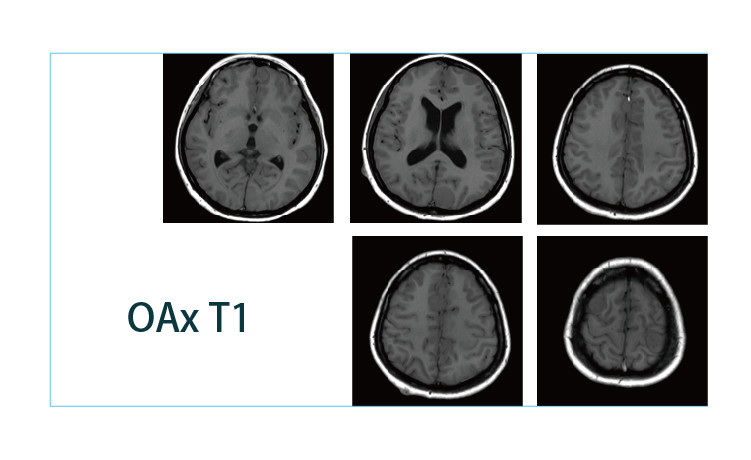

【朗润影像档案】磁共振影像病例分享(编号20190412)